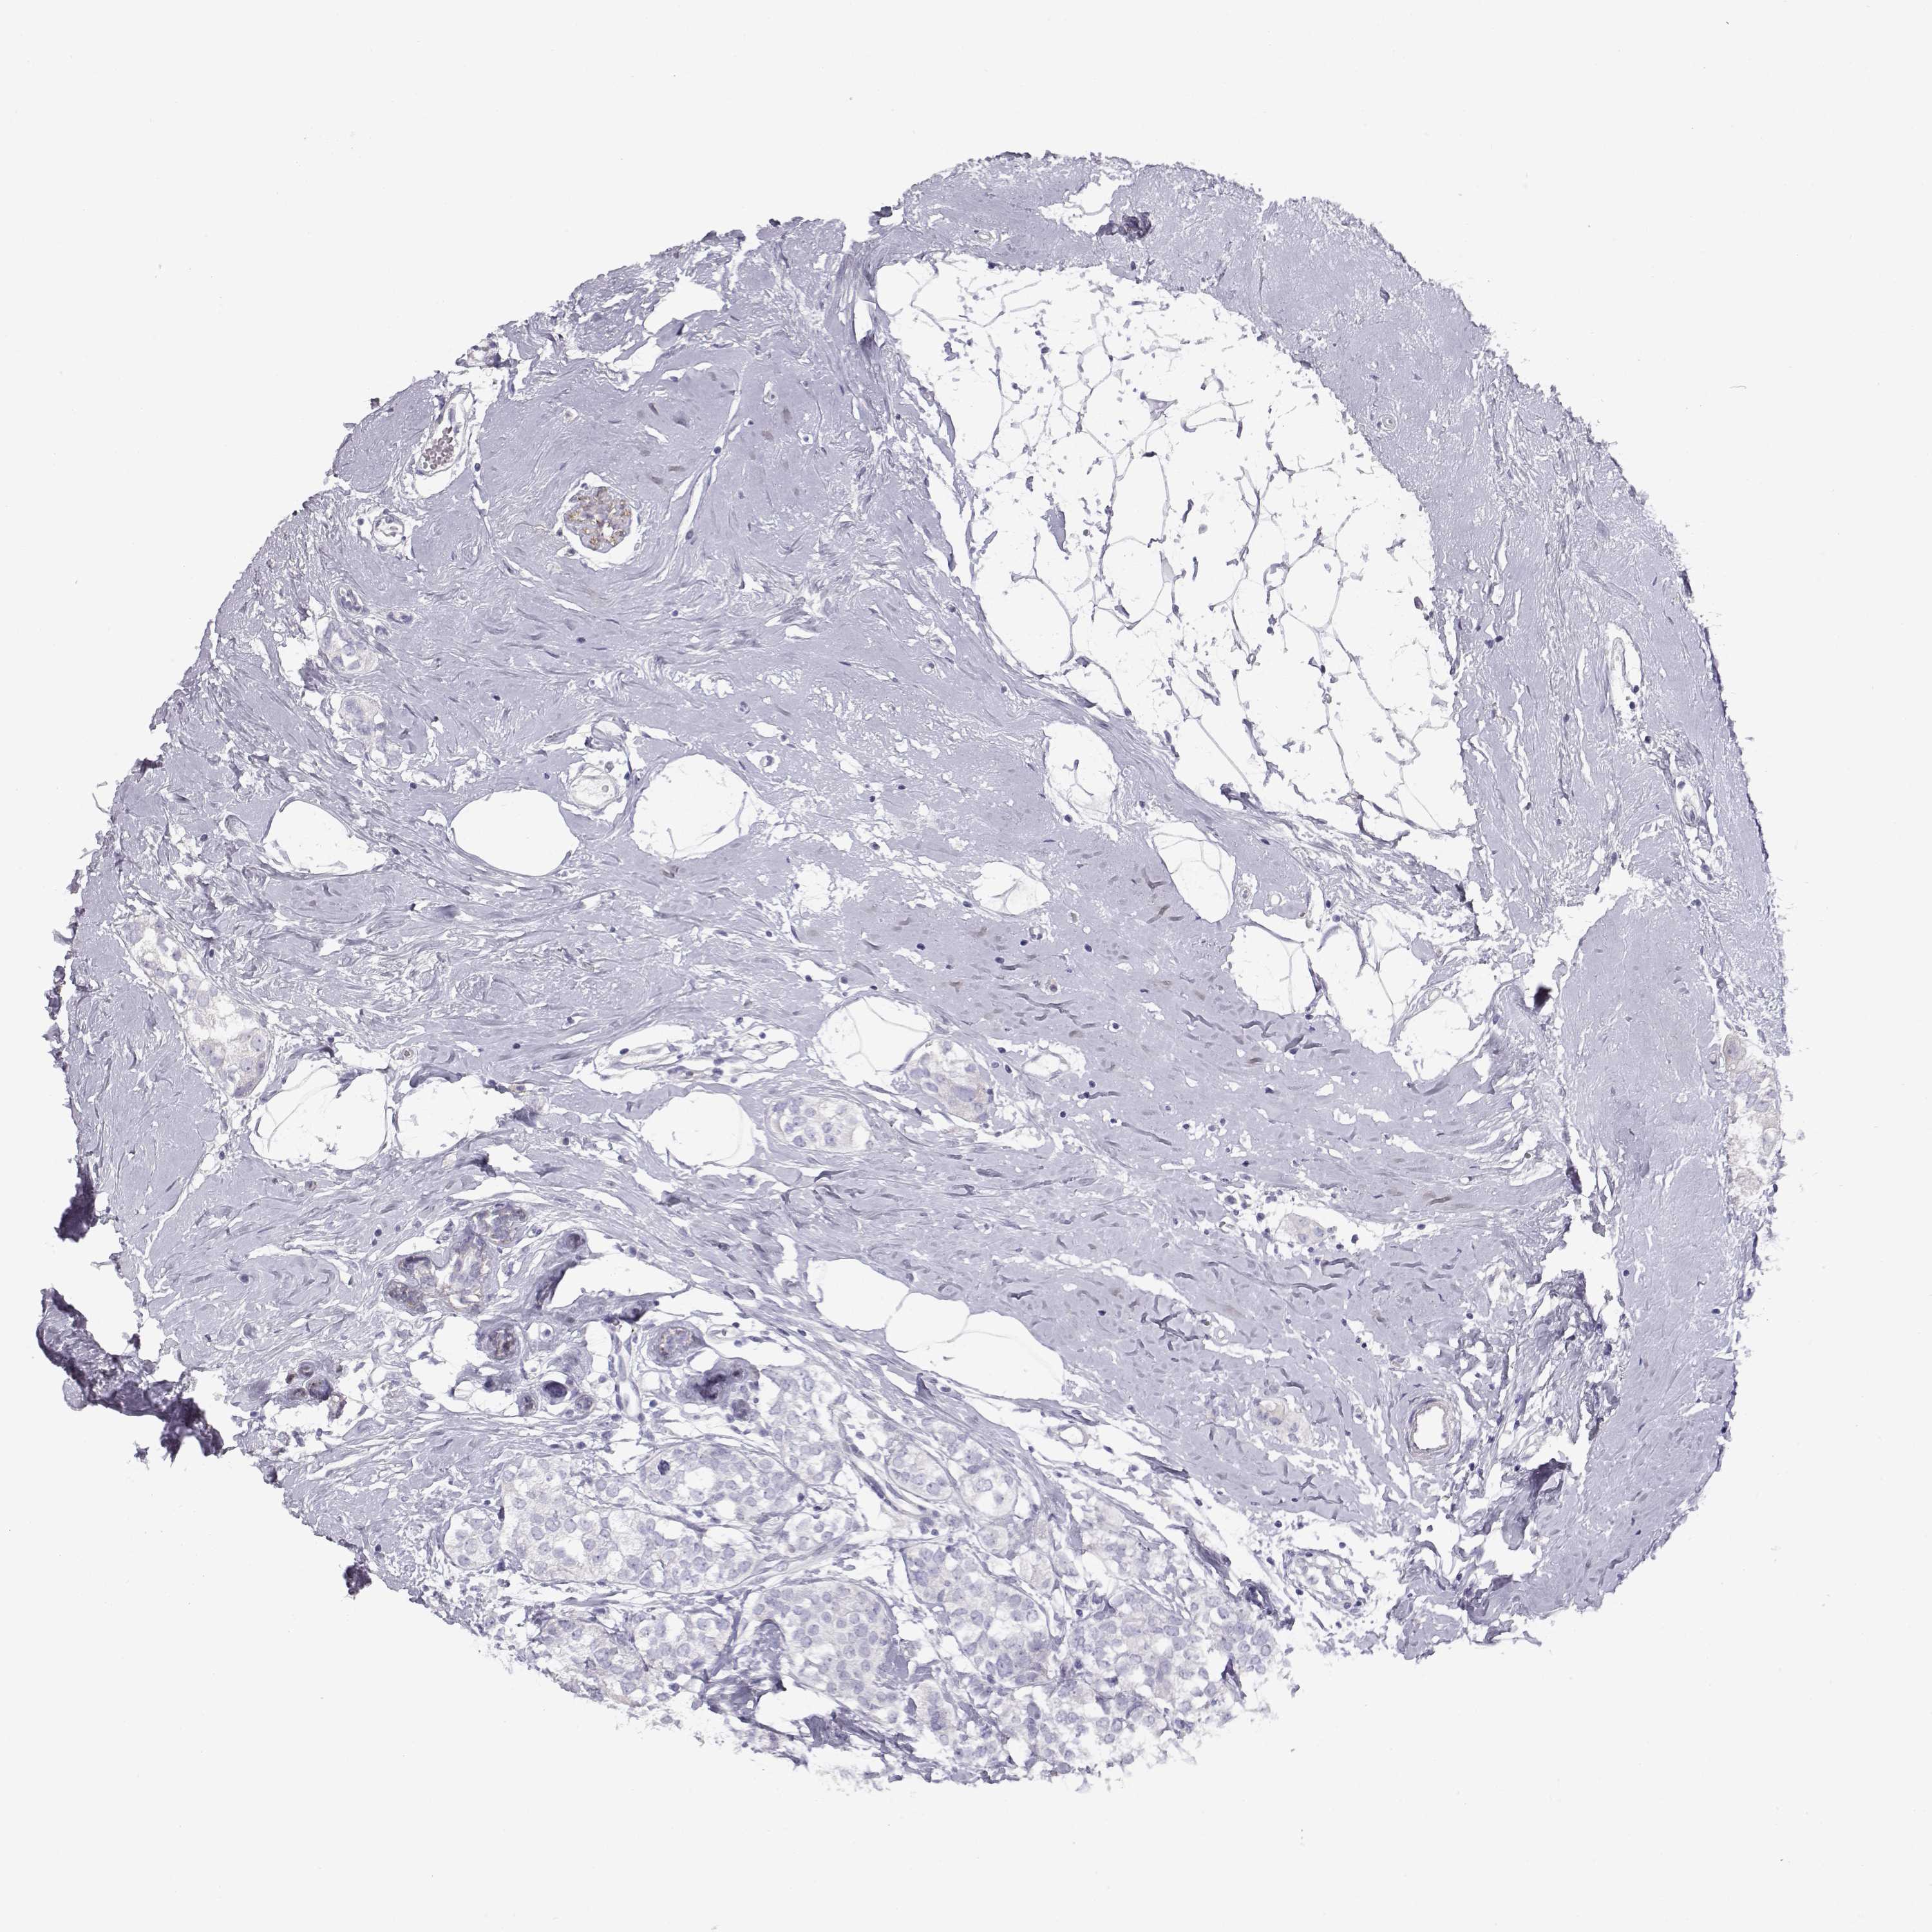

BRCA TCGA BRCA VALIDATION PROTEIN EXPRESSION

Breast cancer

Human cancer